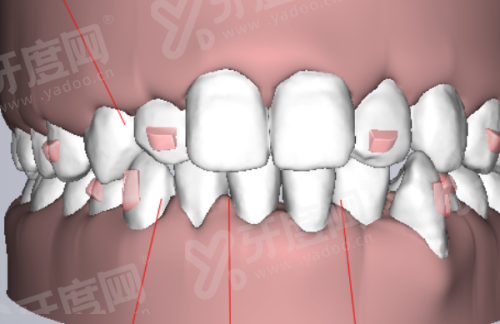

1、江苏拜博口腔医院采用 CBCT 三维影像扫描结合口内扫描技术,能在术前精细重建患者牙槽骨模型,让医生在电脑上提前模拟种植体植入的角度和深度。

2、通过制作个性化手术导板,医生在实操时能实现毫米级精细定位,有效避开重要的神经和血管,大幅降低了术中的出血量和术后的肿胀感。

3、这种技术特别适合牙槽骨条件复杂、多颗缺失或半口全口缺牙的患者,能让手术过程更加微创,修复周期也比传统盲种缩短了不少。